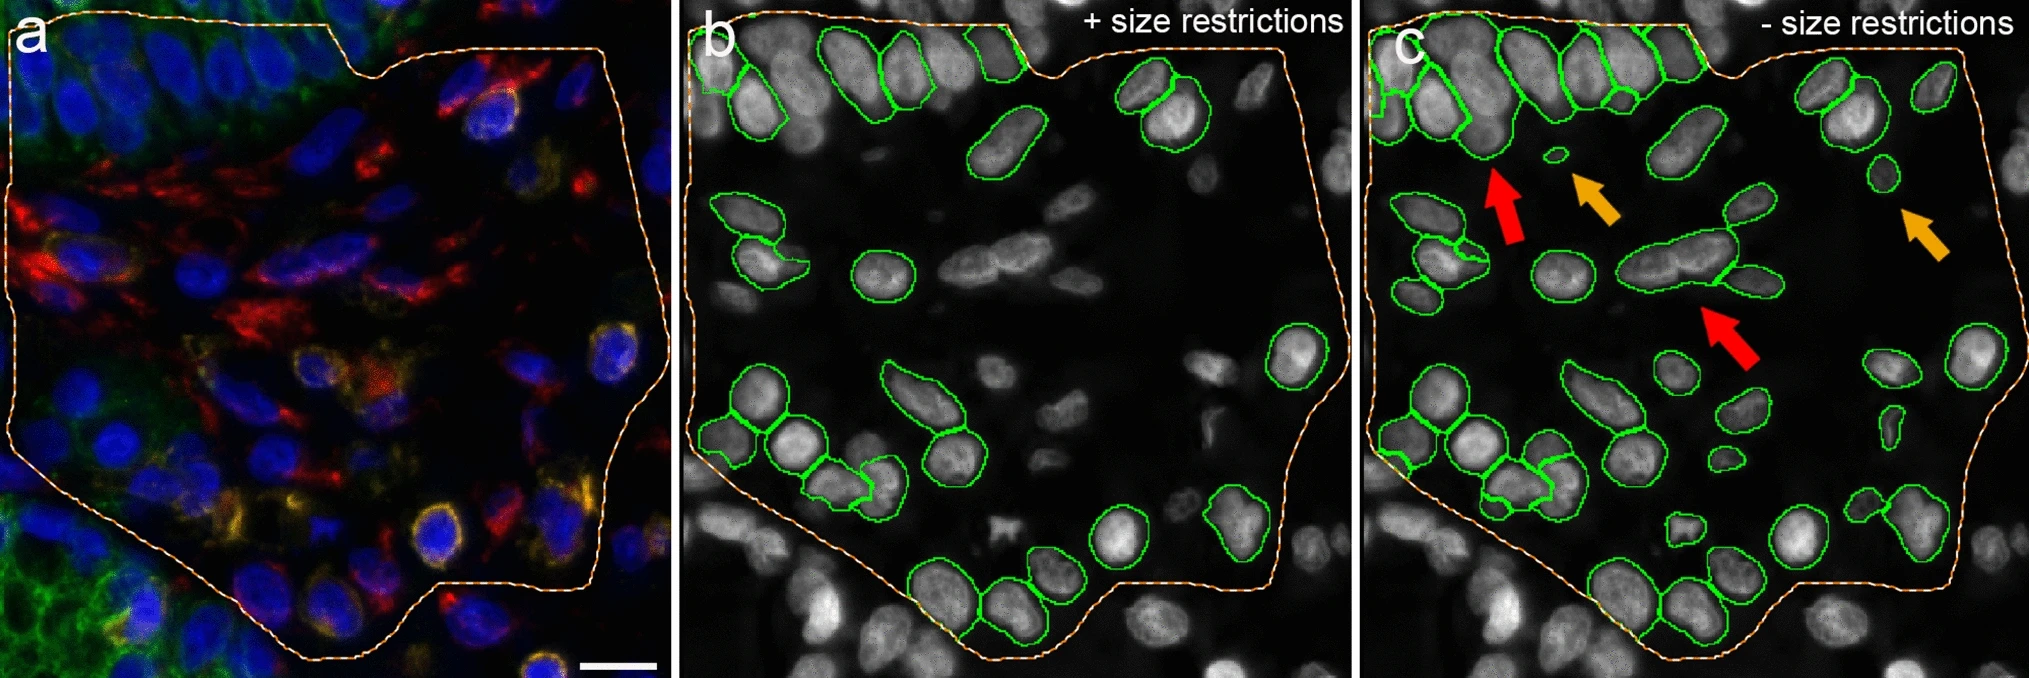

Applications of AI in Cell Segmentation

Accurate cell segmentation is the foundation of tissue cytometry. AI-powered methods, such as deep learning, improve accuracy, reduce errors, and streamline workflows. TissueGnostics integrates AI-based segmentation with phenotyping, spatial analysis, and dot detection.